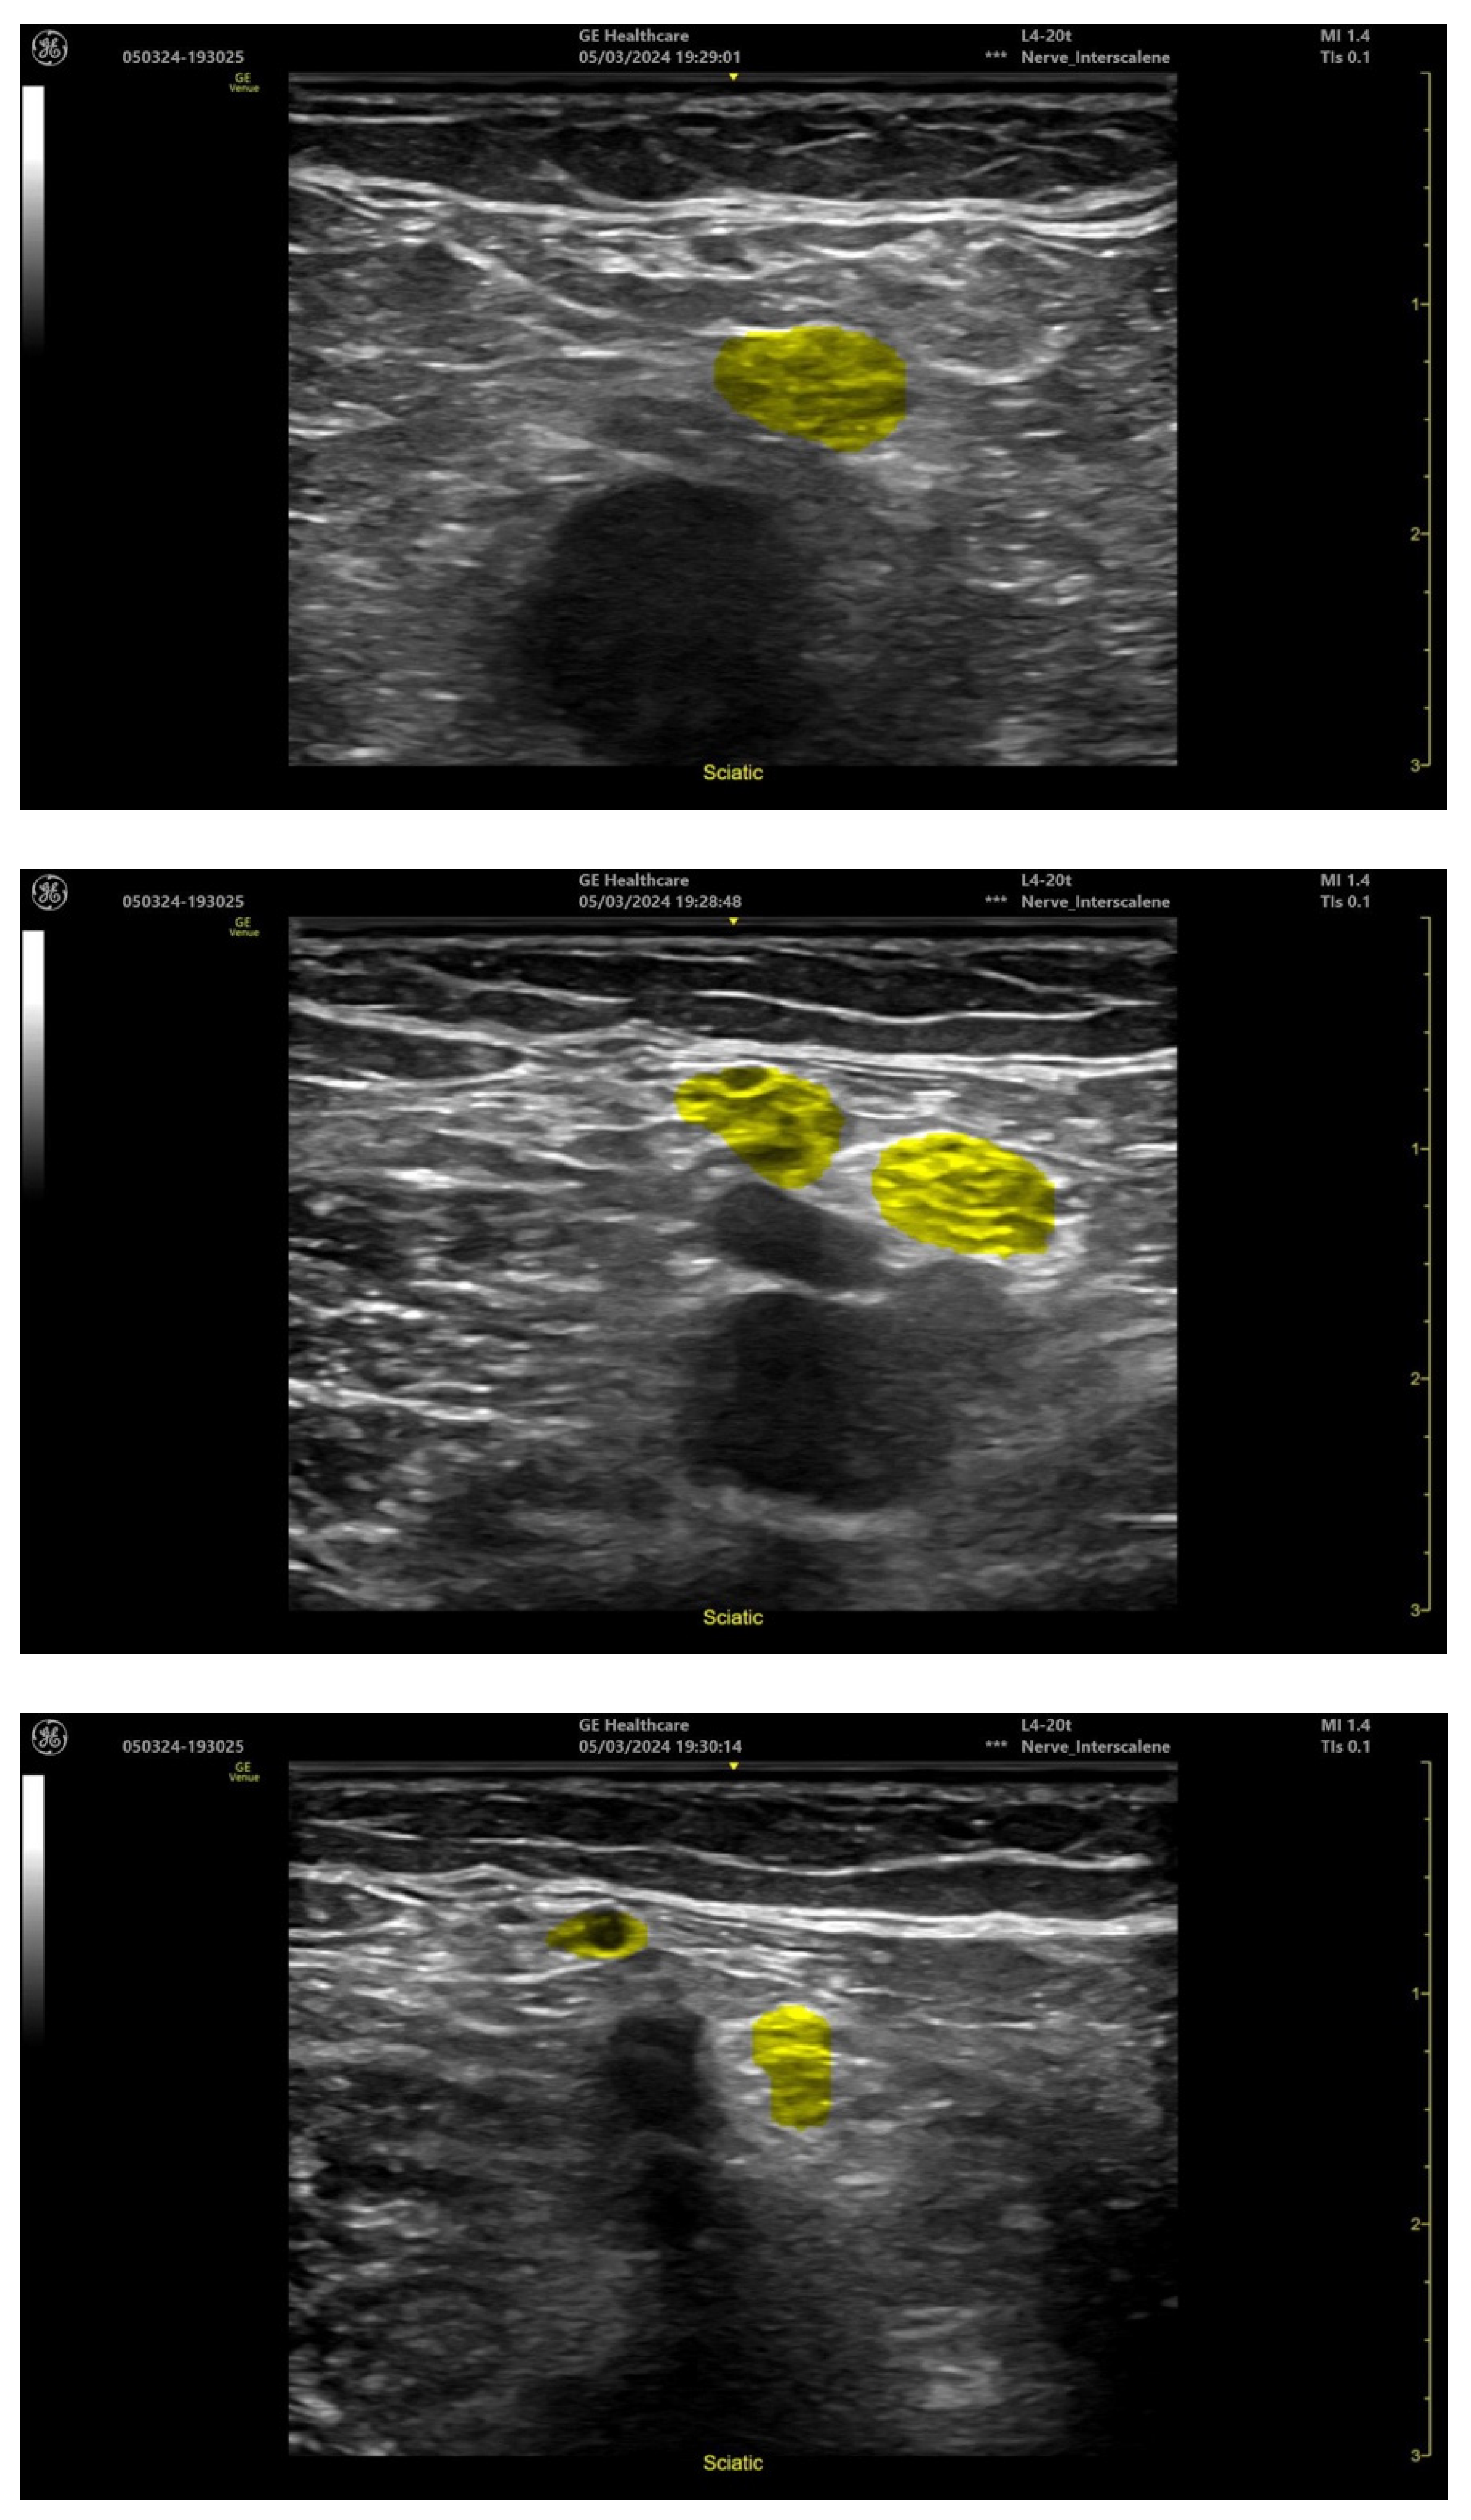

- Delvaux, B. cNerve, AI to Assist in Ultrasound-Guided Nerve Blocks. Available online: https://www.gehealthcare.com/-/jssmedia/gehc/us/files/products/ultrasound/venue-family/whitepaper-cnerve-pocus-venue-family-jb20312xx.pdf (accessed on 1 January 2024).

- Popliteal-level sciatic nerve;